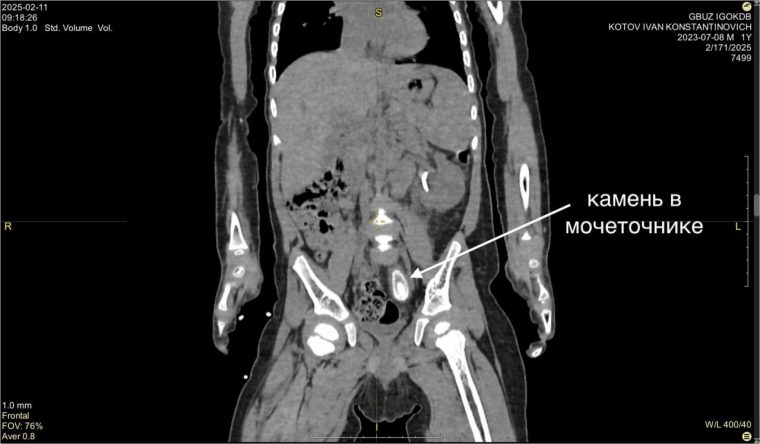

Камень в 3 см удалили из мочеточника маленького жителя Усть-Кута

Сложную операцию провел знаменитый на весь мир иркутский хирург, главный врач Иркутской областной детской клинической больницы Юрий Козлов.

Первые признаки заболевания жительница Усть-Кута обнаружила у сына Вани еще в декабре прошлого года. На обследовании в Иркутске поставили диагноз — большой камень в нижней трети левого мочеточника размером около 3 на 1,5 см и вызванный им блок почки.

Размер камня удивил медиков — это нетипично для таких маленьких пациентов.

— Попытка внутрипросветного лечения была безуспешна — устье мочеточника не пропускало даже самую маленькую оптическую систему цистоскопа. После месяца непростого лечения с использованием нескольких антибиотиков была выполнена операция с применением нашего излюбленного подхода без разрезов — лапароскопии, — рассказывает Юрий Козлов.

Операция прошла успешно, и сегодня Ваня чувствует себя прекрасно.